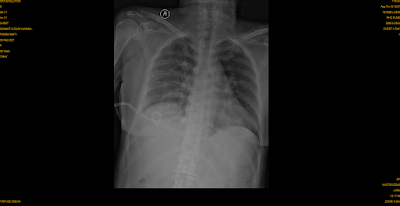

| The Chest Xray shows improvement in opacity and the drain is seen in place |

We managed her with strict control of diabetes via an endocrinologist and drained the pus with help of Pigtail catheter or tube.

Around 550 ml of Pus was drained over a period of four days.